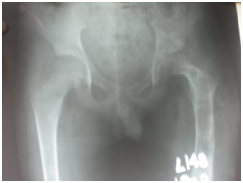

Figure 8&9 Compare initial Radiograph and after completion of treatment.